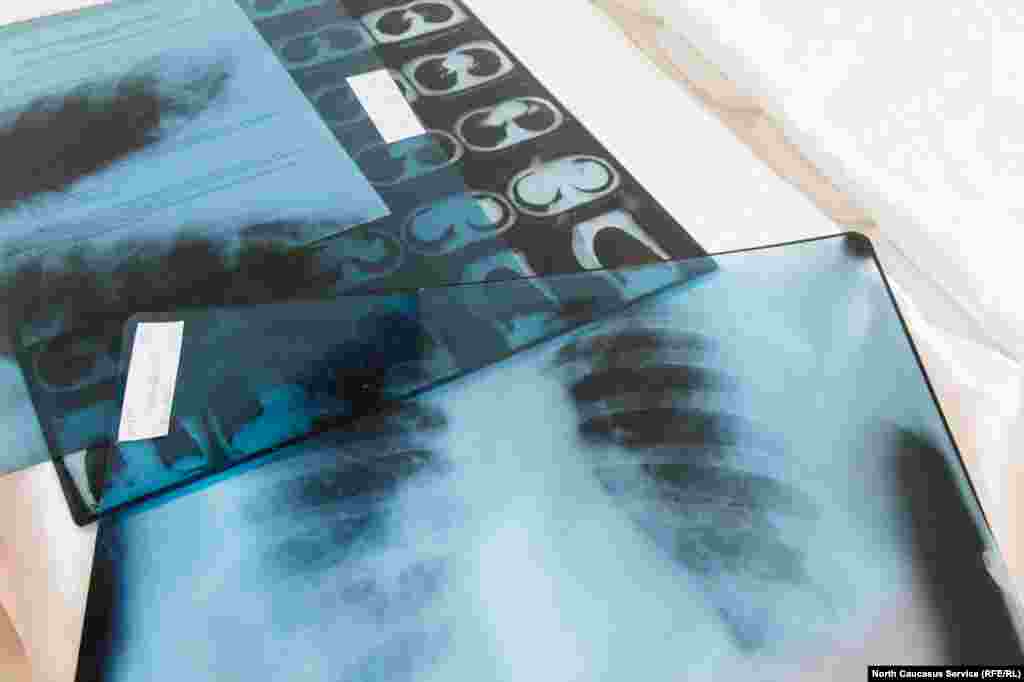

Снимки компьютерной томографии легких одного из пациентов на столе врача "красной" зоны